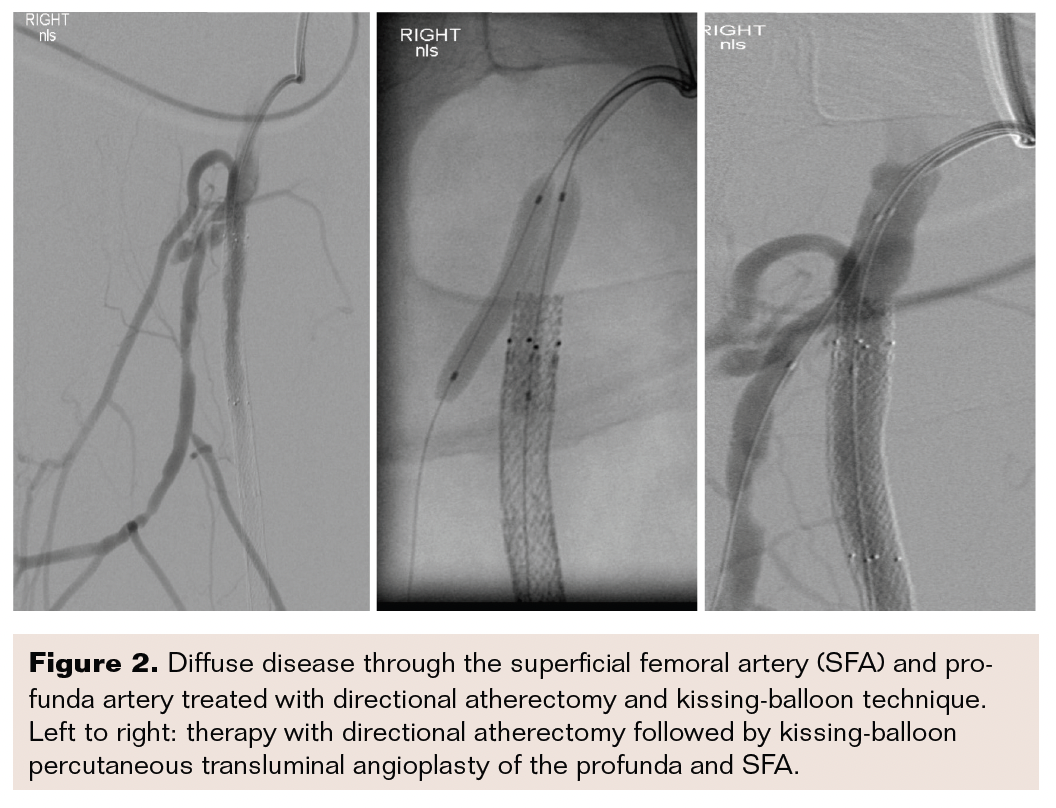

CFA, Profunda, and SFA Disease Vascular Disease Management What Is Sfa Disease Occlusive peripheral arterial disease is blockage or narrowing of an artery in the legs (or rarely the arms), usually due to atherosclerosis and resulting in decreased blood flow. Evaluating the value of drug delivery and the role of permanent implants in treating superficial femoral artery disease. Focussing on the superficial and popliteal artery, there are currently several clinical trials under. What Is Sfa Disease.